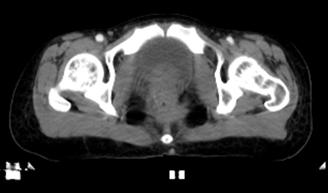

放疗前定位CT

2021-1高姑息放疗:骶前复发病灶放疗。靶区GTV为骶前直肠术后复发病灶,剂量66GY/33F/6w+,盆腔淋巴结引流区(CTV)剂量50.4Gy/28F/5w+。